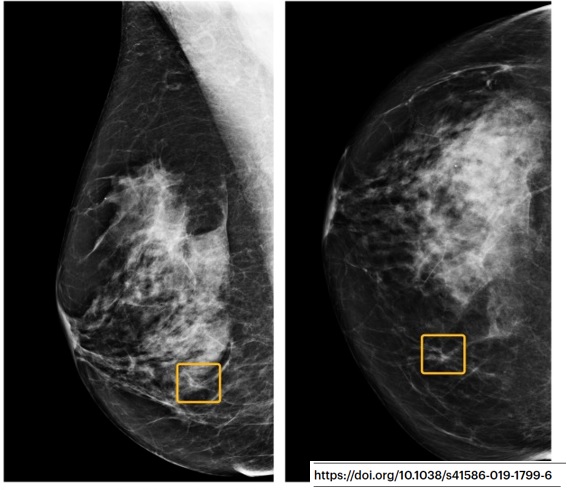

Ca veut pas dire que l’idée est naze ni que le modèle est nul, mais ça veut juste dire que la conclusion ne PEUT PAS méthodologiquement être « le modèle est meilleur que l'humain dans le soin du patient ». Exemple typique dans cet article de Google sur le cancer du sein. (17/32)

« Humain moyen », lecteurs ayant du relire des centaines d’examen rétrospectivement (= pas du tout les conditions cliniques), modèle représenté sur son set de validation interne (sa meilleure performance), etc… Bref.

Ce qui est également intéressant dans ces articles, (18/32)

c’est que la « taille de l’effet » n’est pas prise en compte dans les résultats. Par exemple, on considère de façon équivalente ce gros cancer (à gauche), vu par 6/6 radiologues mais pas par le modèle (!), et cette toute petite lésion vue par 0/6 radiologues. (19/32)

Mais dans la vraie vie ? Est-ce que la première aurait été plus agressive ? Est-ce que la deuxième aurait dû être traitée ou pas ? Ca grossit sur la mammo suivante ? Quel âge ? Quel sous-type histologique ? Bref, les patientes disparaissent au profit des images isolées. (20/32)